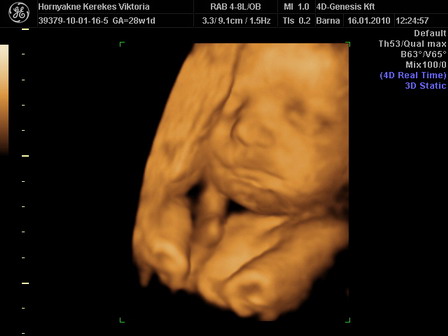

A nagy hír, hogy megint kis kukis van a pocakban. :-) Mindene megvan és egészséges, bár nem lett jó az AFP-m de megnéztek még egy értéket ami viszont jó lett + a genetikai uh. is jó. Így minden rendben van velünk.

Megbeszéltük a 4D-t is és az áprilisi fizunál megyünk. Igaz akkor már 30 hetes leszek, de látva néhány 30 hetes képet, amik nagyon szuperek lettek, nem aggódok :lol: :lol: